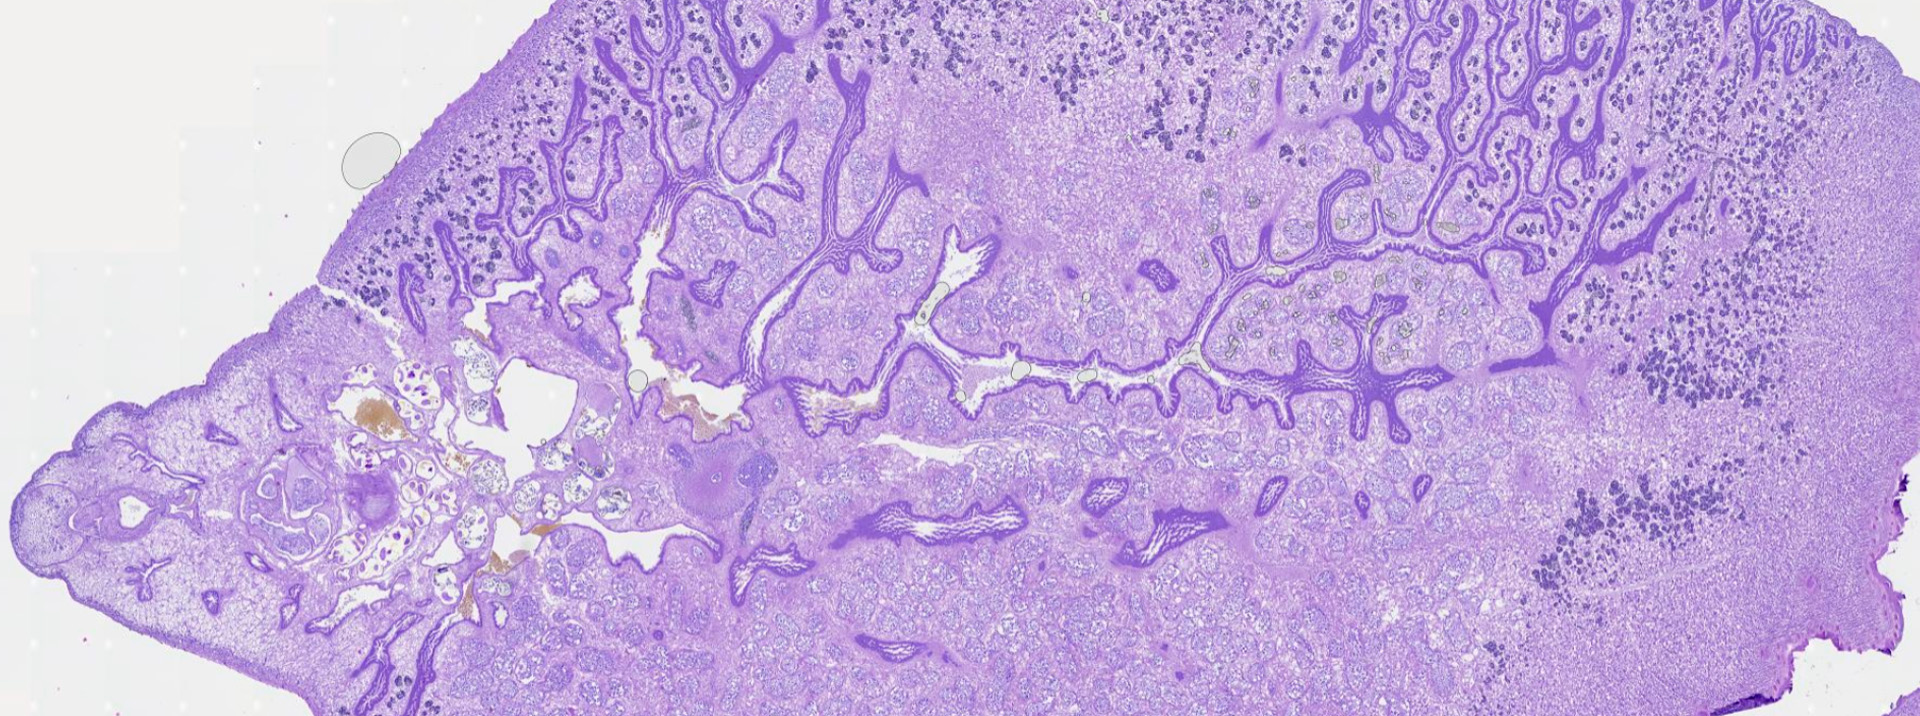

IMAGEN ESCANEADA

Strongyloides

https://pathpresenter.net/public/display?token=d9f0840c

Strongyloides stercoralis

CARACTERÍSTICAS: Nematodo único con la capacidad de alternar entre un ciclo de vida parasitario y un ciclo de vida libre en el suelo (facultativo), además de poder perpetuarse en el hospedero mediante autoinfección.

• Hembra Parásita (Partenogenética): Filiforme, mide 2.5–3 mm. Es la única forma adulta en el ciclo parasitario. Se reproduce por partenogénesis (sin fecundación) en la mucosa del intestino delgado.

• Larva Rabditiforme (L1): Mide 250 µm. Presenta un esófago rabditoide (con bulbo esofágico). Eclosiona de los huevos dentro de la mucosa intestinal y es la forma que se elimina en las heces. Es una etapa no infectante y de alimentación.

• Larva Filariforme (L3): Mide 500–600 µm. Es la forma infectante. Presenta un esófago filiforme (largo y recto) y una cola bifurcada (muesca). Se desarrolla en el suelo a partir de L1, o en el lumen intestinal (autoinfección), y penetra activamente la piel del hospedero.